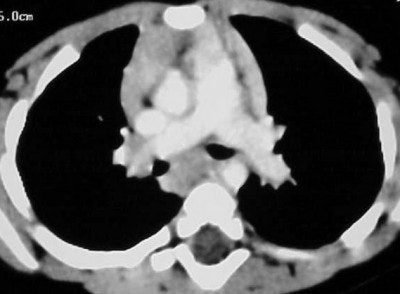

Figures CT 1 and CT 2 are 8 cc of Visipaque hand-injected into a 12-year-old girl through a 22-gauge IV with a 15-second delay. Figure 1 shows good opacification of the pulmonary arteries while figure 2 shows the abdominal aorta clearly and the spleen and liver in the arterial phases.